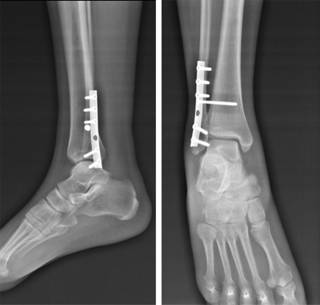

Resumen Este procedimiento quirúrgico se utiliza para corregir una fractura del peroné o de la tibia en la articulación del tobillo El procedimiento consiste en la fijación de una placa de fijación de acero inoxidable o titanio al peroné y el uso de tornillos o placa de fijación en la tibia para estabilizar los huesos y permitir la curación. Por ejemplo, una fractura en el extremo del peroné se llama fractura de maléolo lateral, o si tanto el peroné como la tibia se rompen, se denomina fractura bimaleolar Dos articulaciones están involucradas en las fracturas de tobillo Articulación del tobillo donde se encuentran el peroné, la tibia y el astrágalo Articulación de sindesmosis articulación entre el peroné y la tibia, que se mantiene unida mediante ligamentos. Son indirectos y van a dar lugar a los esguinces de tobillo y a las fracturas maleolares (tibial, peroneo) Traumatismos por compresión axial (indirectos) tenemos las fracturas del pilón tibial (es el segmento distal de la tibia, a nivel supramaleolar) o las fracturas del calcáneo (fractura de los amantes, es la típica del medio laboral).

Muchos pacientes acuden a IICOP, con secuelas de fractura de tobillo, generalmente tipo B y C de WeberEn la mayoria de los casos estas secuelas se han producido por una inadecuada estrategia de tratamiento, en los que se no se han aplicado los principios básicos de reconstrucción anatómica completa de todos los componentes de la articulación. La tibia es el nombre que recibe el hueso más largo de la pierna Su extremo superior presenta dos eminencias óseas que se articulan con los cóndilos femorales que encajan conformando la rodilla, mientras que su extremo inferior forma el maléolo interno o prominencia interna del tobillo. CIE10 Сódigo S para Fractura de la pierna, inclusive el tobillo Incluye maléolos Las siguientes subdivisiones se ofrecen para uso opcional, como carácter suplementario, cuando no es posible o no se desea usar la codificación múltiple para identificar las fracturas con heridas;.

A sus 64 años, Luis vende paletas para atender su fractura de tobillo por lo que ahora requiere el apoyo de la ciudadanía para poder atender la fractura de tibia, peroné y tobillo. Fractura de la extremidad distal de la tibia (fractura de tobillo), esta última pueden ser simple, bimaleolar o trimaleolar Se llaman fracturas del pilón tibial a aquellas que afectan a la extremidad distal de la tibia, es decir al sector de la tibia más próximo al pie, pero por encima de los maleolos. Muchos pacientes acuden a IICOP, con secuelas de fractura de tobillo, generalmente tipo B y C de WeberEn la mayoria de los casos estas secuelas se han producido por una inadecuada estrategia de tratamiento, en los que se no se han aplicado los principios básicos de reconstrucción anatómica completa de todos los componentes de la articulación.